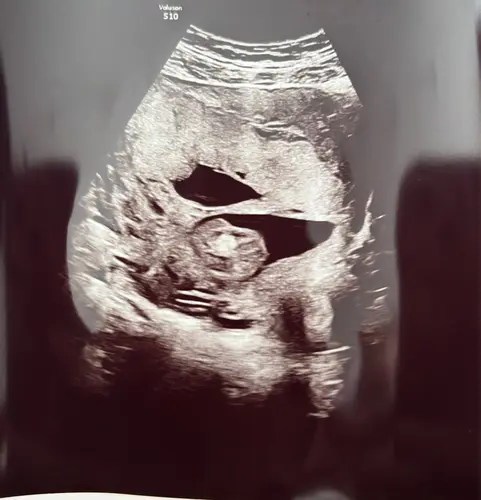

Vandaag extra echo gehad, streng zit gelukkig meer aan de zijkant en zal geen gevaar meer voor der zijn. Vingertjes etc zijn goed ontwikkeld.

Ze gaf aan omdat er bij mij bloedvaatjes doorheen lopen ze het extra willen controleren maar het er voor nu goed uit ziet.

Jammer genoeg een oud bericht, maar ook wel heel benieuwd. Bij mij was de streng (van voor naar achter) op de 13 weken echo al gezien, was met 15+3 nog zichtbaar en heb maandag de 20 weken echo. Die ik hierdoor wel heel spannend vindt, ondanks dat de gynaecoloog aangaf dat ik me er totaal geen zorgen over hoefde te maken.